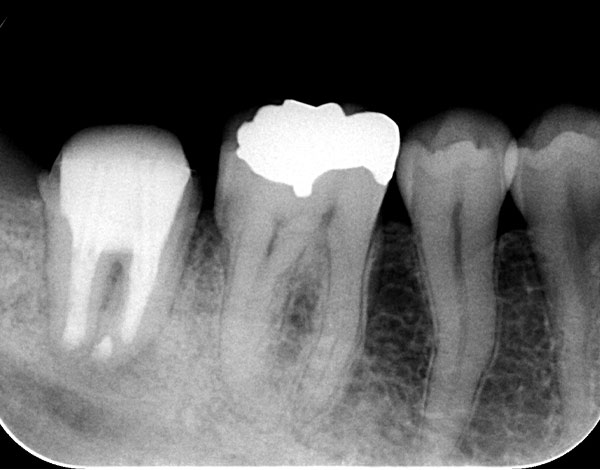

• 治療前

• 治療後

他院にて破折の疑いがあるため経過観察をしていたが、積極的な治療を希望されて来院された患者さんです。マイクロスコープで根管内を確認してみると、破折線を認めましたが、骨透過像の位置とは異なるため根管治療を行いました。治療後6か月経過時のCT像ですが骨の回復が認められます。根管治療の費用は88,000円です。